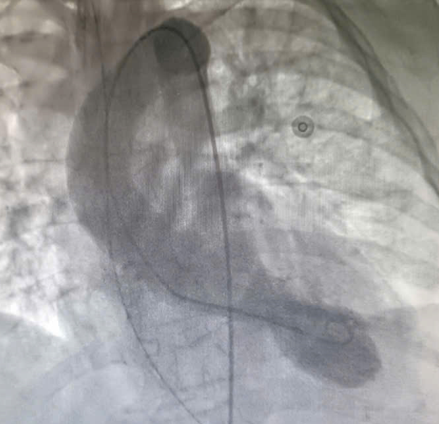

| Trước: Hình chụp tâm thất trái cuối tâm thu. Sau: Cuối tâm trương – giảm động vùng mỏm và tăng co bóp ở vùng đáy - Ảnh BVCC |

Ngày thứ 4 sau nhập viện, các triệu chứng của nhồi máu cơ tim cấp tính đột ngột xuất hiện: Biến đổi điện tim (Hình ảnh ST chênh tại toàn bộ các đạo trình thành trước tim); siêu âm tim ghi nhận phân suất tống máu (EF) giảm xuống 56%, thất trái giãn rộng, giảm vận động nặng ở vùng giữa và mỏm tim, xét nghiệm men tim tăng cao.

Mặc dù chụp mạch vành không phát hiện tổn thương tắc nghẽn, các bác sĩ tiếp tục quyết định chụp hình ảnh buồng tim. Kết quả cho thấy rối loạn vận động điển hình của hội chứng Takotsubo, với tăng co bóp ở đáy và giảm vận động ở mỏm tim, xác định đây là bệnh cơ tim cấp do căng thẳng.